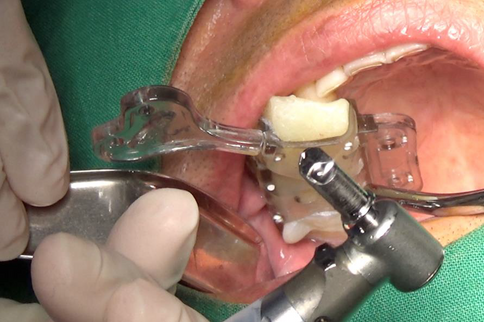

#16 Extraction and place VAROGuide into oral cavity.

Safe sinus augmentation was performed using VAROGuide and VAROGuide Sinus Kit.